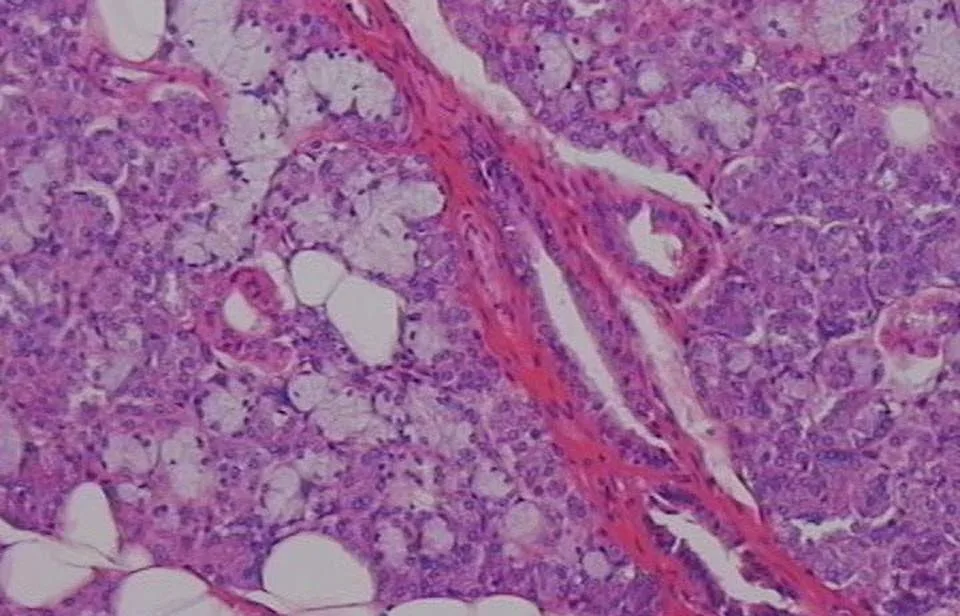

Oι ερευνητές του ερευνητικού κέντρου RIKEN και του Πανεπιστημίου Σόγουα, που έκαναν τη σχετική δημοσίευση στο περιοδικό «Nature Communications», χρησιμοποίησαν ένα ‘κοκτέιλ’ χημικών ουσιών για να «χειραγωγήσουν» εμβρυικά βλαστικά κύτταρα, ώστε να δημιουργήσουν το στοματικό εξώδερμα από το οποίο αναπτύσσονται οι σιελογόνοι αδένες.

Στη συνέχεια, οι επιστήμονες μεταμόσχευσαν αυτό το εργαστηριακό οργανοειδές του σιελογόνου αδένα στα πειραματόζωα, μαζί με μεσεγχυματικό ιστό, έναν άλλο εμβρυικό ιστό, ο οποίος δημιουργεί τον συνδετικό ιστό ανάμεσα στους σιελογόνους αδένες και στους άλλους ιστούς όπως ο νευρικός.